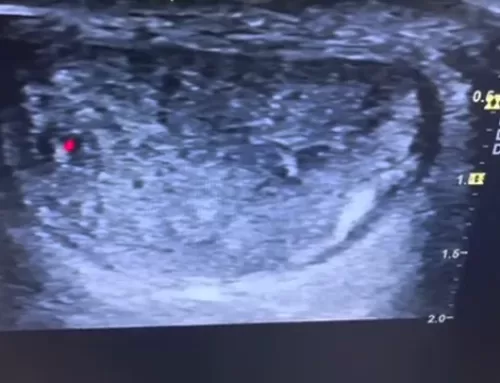

However, deeper ultrasound imaging reveals a prominent bony bump, known as insertional Achilles tendinopathy, which is the true source of the patient’s pain and swelling. The affected heel shows irregular bone structure, hypoechoic (dark) areas, and localized inflammation right at the pain point.

The comparison with the other (non-painful) side shows only minor tendon changes, confirming that the extra bone and tendon irregularity at the insertion point is the root cause of discomfort. This video is a great resource for understanding less obvious causes of heel pain and how ultrasound imaging can reveal hidden structural issues often missed in a surface-level exam.